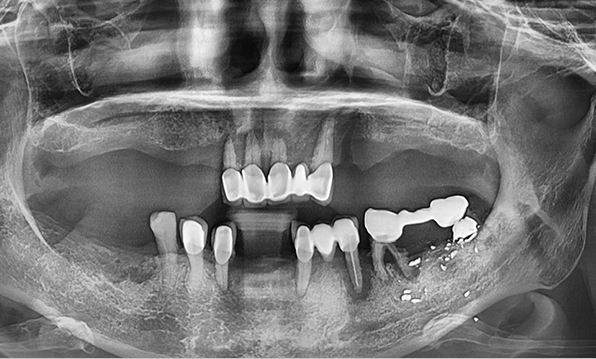

전체 임플란트는 위턱과 아래턱의 교합, 잇몸뼈의 상태 및

얼굴 변화 등 모든 것을 고려해 식립해야 합니다.

서울더자연치과는 3D 디지털 기술의 정밀 진단을 바탕으로

수술 계획을 세워 수술을 집도합니다.

잇몸뼈가 얇은 상태

-

잇몸뼈 충분히 이식 후 임플란트 식립

성공을 위한 노하우, 잇몸뼈 재건 기술

전체 임플란트를 해야하는 환자들은

대부분 고령의 환자들로 오랜 틀니 사용

또는 노화로 인해 치조골이

거의 남아있지 않는 경우가 많습니다.

이 때, 치조골 이식을 병행하여 잇몸뼈 재건 후 안정적인 임플란트 식립을 하고 있습니다.

치료기간 : 2021.04.12~2021.09.15